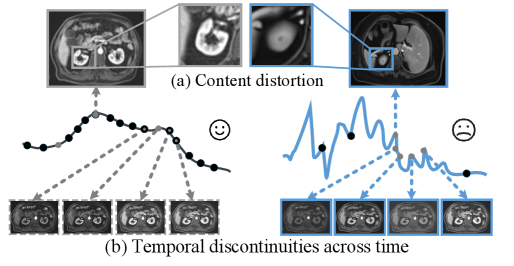

A practical compromise is to directly train a generative model on a sparsely sampled dataset in an attempt to capture the underlying contrast-agent kinetics. However, this strategy suffers from two fundamental limitations: (a) Content distortion in the spatial dimension. Owing to the absence of ground-truth frames at the missing time points, the model receives no supervision on the true anatomical state. Once overfitting occurs, it produces the distortions illustrated in Fig. 2(a), including structural deformation and organ misalignment. Although prior-based regularization [26, 1, 61, 43, 88] can encourage more realistic content at unsampled times, such priors still fail to preserve patient-specific anatomical details. (b) Discontinuity in the temporal dimension. Without continuously sampled data, the model is unable to learn the true kinetic law of the contrast agent, leading to mismatches with time conditions and temporal jumps between adjacent frames, as shown in Fig. 2(b). While post-hoc smoothing [30, 16, 27, 45] reduces visible discontinuities, pixel-space smoothing inevitably blurs fine details and deviates from the actual kinetics.

Refer to caption

Figure 2: Limitation: MRI Acquisition-induced low temporal resolution in MRI CEKWorld leads to (a) Content distortion and (b) Temporal discontinuities across time.